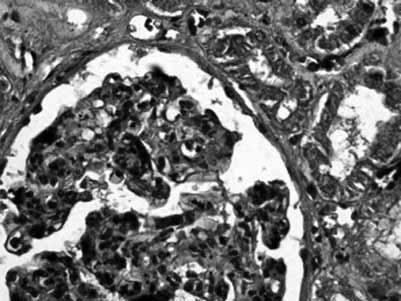

Patoloogia valdkonnas on koostatud neli värvimisjuhendit: „Van Giesoni värvingumeetodi juhend …“ (2016), autor H. Leping; „Elastsete kiudude värvingu juhend …“ (2017), autor E. Luik; „Neerukoe histoloogilise värvingu juhend …“ (2018), autor E. Oja; ning „Maksa histoloogilise värvingu metoodiline juhend …“ (2018), autor O. Mamošina. Kõik nimetatud juhendid haaravad histoloogiliste preparaatide värvinguid. Esimene kord ebaõnnestus üliõpilastest ekspertidel E. Oja väljavalitud Masson trikroomi värvingumeetodi katsetamine, kuid edaspidi täpsustati loputamisetappi pärast töötlust happelise fuksiinilahusega. Seejärel üliõpilaste katsetused õnnestusid (joonis 2).

Joonis 2. Nooremad üliõpilased kasutasid neerukoe värvimiseks koostatud Masson trikroomi värvingu juhendit (E. Oja) ning said kena sinistes ja punastes toonides neerukoe pildi